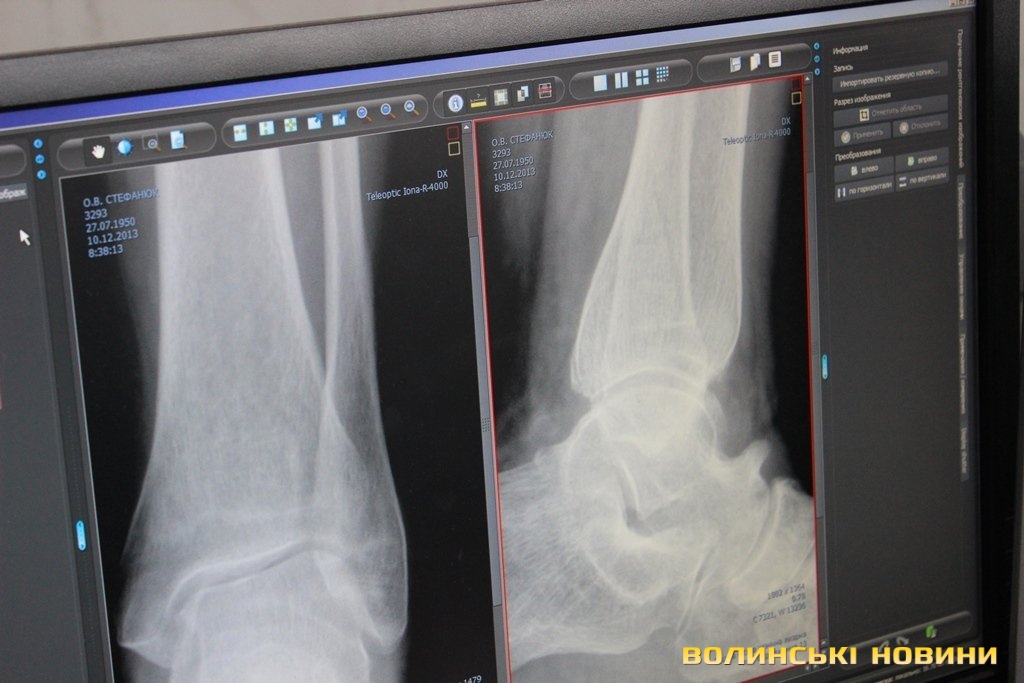

Травмовані заходять по черзі, але людей з різким болем пропускають першими. До слова, нещодавно тут почали працювати на новій цифровій апаратурі, для якої не потрібні одноразові плівки та й опромінювання менше. Рентген-лаборант Валентина Окопна каже: «Це пришвидшує прийом травмованих, бо ж не доводиться чекати, як в старинку, півгодини на результат сканування. Тепер рентгенівські результати миттєво отримує лікар на своєму комп’ютері, де може знімок збільшувати в рази і детально розглядати».